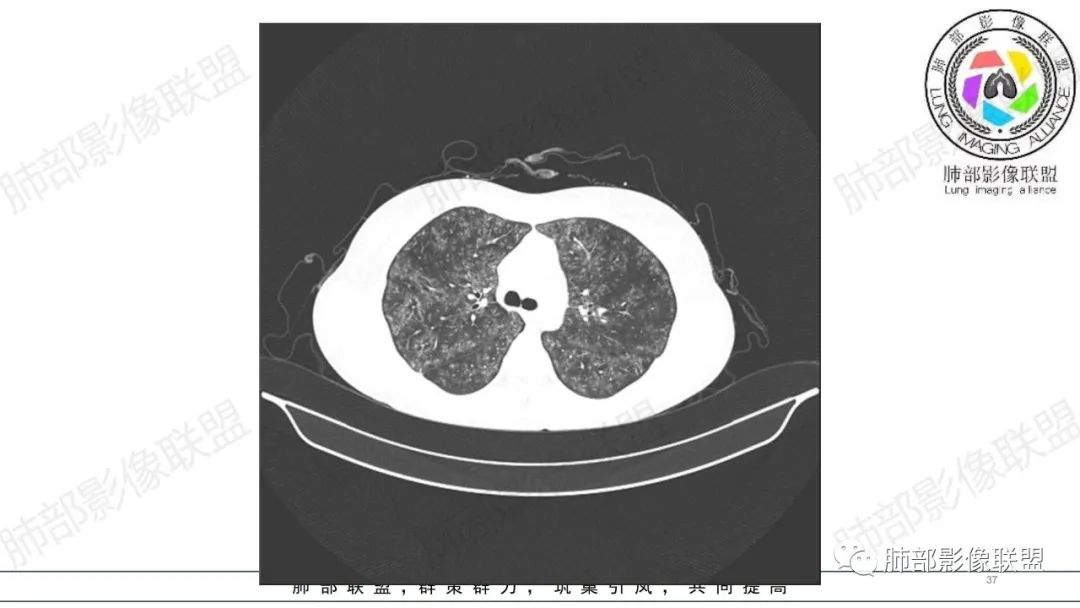

34岁女性患者,“哮喘”病史30年,近期有可疑刺激性气体吸入史;因乏力半年,咳嗽、憋气、发热4天就诊;6.1CT提示双肺广泛毛玻璃影及粟粒样结节,胸膜下闲置及血管周闲置,可见树丫征,部分小叶间隔增厚。考虑:1.过敏性肺泡炎,有可疑刺激气体接触史,胸膜下闲置,广泛毛玻璃影,地图样分布,粟粒结节边界模糊,支持过敏性肺泡炎,但糖皮激素治疗效果不佳,且动态复查血常规血红蛋白进行性降低,过敏性肺泡炎 不符合;2.肺含铁血黄素沉积症:患者30“哮喘”病史,可能为肺含铁症状,肺部CT提示双肺弥漫毛玻璃影及粟粒结节影,中下肺明显,肺底部分小叶间隔增厚,近期咳嗽、憋气、发热,血常规血红蛋白进行性下降,考虑肺含铁急性期症状,但临床无咯血症状,肺含铁不典型。综合考虑:肺含铁血黄素沉积症>过敏性肺泡炎。

年轻女性 ,急性喘息发热,肺部影像弥漫磨玻璃密度,部分细小腺泡结节,胸膜下黑线显示,短期复查,病变密度增高,下肺明显,血管周围肺组织累及较少、且逐渐成小叶间隔分布。考虑弥漫肺泡内病变,并经淋巴道转移,下肺比上肺明显,多为免疫细胞功能下肺较强。1.过敏性肺泡炎,有相关病史,三层密度特点、头尾测分布,符合。2 肺泡微石症,多有钙化,且缓慢起病,病程不太符合,放待排。3 吸入相关肺损伤,有病史,疾病演变过程也符合渗出-肉芽肿改变,建议详细询问病史。4 感染性病变,结核?病变气道分布为主,如此弥漫且没有树丫不符合。5.巨细胞病毒,可以磨玻璃 结节 改变,没有免疫缺陷病史。最后考虑吸入所致 1过敏性肺泡炎、吸入性肺损伤 鉴别肺泡微石症。

肺内气腔磨玻璃结节,肝脾肿大,治疗后间质改变,弥漫大B可能